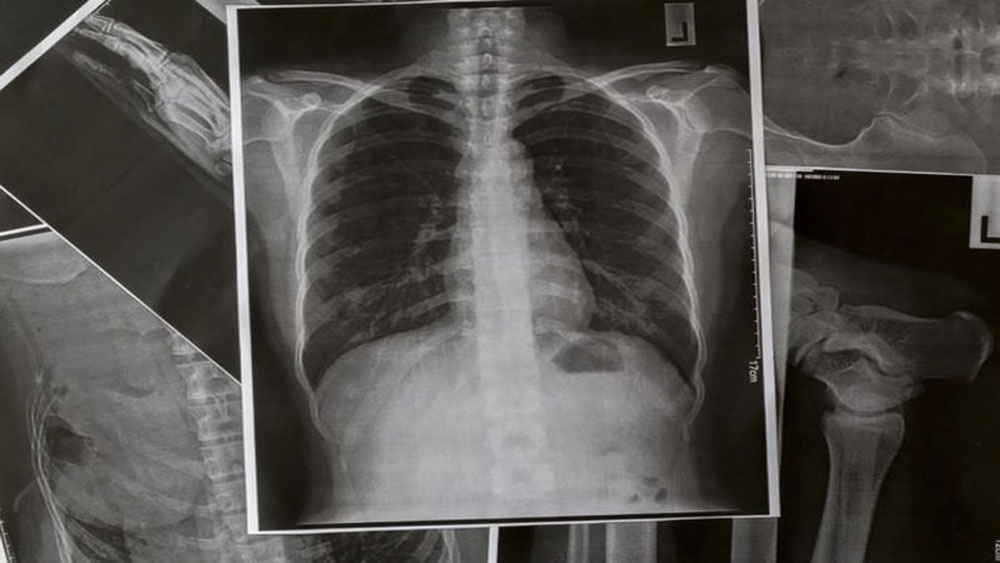

Người Việt lười ăn rau là nguyên nhân gây 2 bệnh ung thư phổ biến

57% người trưởng thành tại Việt Nam ăn thiếu rau và trái cây so với khuyến nghị của WHO, trong khi ăn rất nhiều thịt.